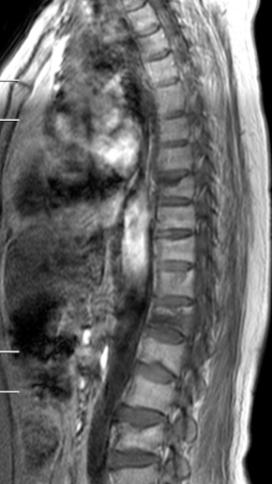

今年6月,63岁的华阿姨因“不慎摔伤致胸腰部疼痛剧烈、无法活动”到我院急诊科就诊,X线检查提示 “胸8.12椎体压缩骨折”,随即收入我院创伤外科住院治疗。完善胸椎CT、MR等后,刘志祥主任带领科室团队迅速为患者制定了个性化治疗方案,并向家属详细介绍病情、各种治疗方案利弊和国内外最新进展后,患者及家属均表示愿意接受微创椎体成形术治疗。

术前核磁共振检查明确T8.12椎体骨折,为疼痛责任椎体;经皮穿刺微创椎体成形术后复查可见椎体高度恢复良好,骨水泥弥散满意。